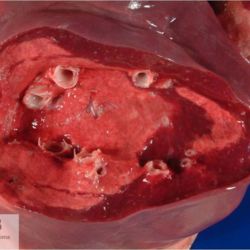

Pàgina anterior de 637 Pàgina següent 3181 total Ovine Specie: Ovine Organ: Brain Lesion: Meningitis Lesion modifier: Meningitis - Fibrinous-purulent Disease: - Not viewed Ovine Specie: Ovine Organ: Lung Lesion: Atelectasis Lesion modifier: - Disease: - Files/Expedient: Leon15 Position: 136 (2 views) Ovine Specie: Ovine Organ: Lung Lesion: Atelectasis Lesion modifier: - Disease: - Files/Expedient: Leon15 Position: 87 (3 views) Ovine Specie: Ovine Organ: Lung Lesion: Bronchitis Lesion modifier: - Disease: Dictyocaulosis Files/Expedient: Leon12 Position: 253 (1 views) Bovine Specie: Bovine Organ: Lung Lesion: Bronchopneumonia Lesion modifier: Bronchopneumonia - Catarrhal-purulent Disease: - Position: 253 (1 views) Pàgina anterior de 637 Pàgina següent Títol Select...Avian (Exotic) (110)Avian (Poultry) (76)Bovine (317)Canine (935)Caprine (47)Equine (257)Feline (326)Ferret (19)General (127)Marine mammal (22)Non-human primate (20)Ovine (328)Porcine (379)Rabbit (61)Reptile (38)Rodent (28)Wildlife (91) Format Select...- (60)Abomasum (37)Adrenal gland (10)Blood (7)Blood vessel (50)Body as a whole (19)Bone (57)Bone marrow (21)Brain (93)Cloaca (1)Diaphragm (2)Ear (5)Esophagus (39)Eye (16)Fetus (12)Gallbladder (23)Gizzard (2)Heart (265)Intestine (356)Joint (32)Kidney (443)Larynx (5)Liver (326)Lung (264)Lymph node (91)Mammary gland (10)Mediastinum (1)Muscle (22)Nasal cavity (22)Nerve (7)Omasum (5)Oral cavity (63)Ovary (14)Oviduct (8)Pancreas (7)Parathyroid (5)Penis (10)Peritoneum (65)Pharynx (9)Pituitary gland (6)Placenta (7)Prostate (8)Proventriculus (3)Reticulum (1)Rumen (28)Sinus (7)Skin (181)Spinal cord (15)Spleen (105)Stomach (125)Teeth (1)Testicle (11)Thoracic cavity (31)Thymus (13)Thyroid gland (5)Tongue (32)Tonsils (11)Trachea (11)Urethra (5)Urinay bladder (61)Uterus (27)Vagina (1)Vulva (1)Yolk sac (1) Cobertura Select...- (152)Abomasitis (26)Abscess (27)Acidosis (1)Adenocarcinoma (20)Adenoma (9)Aerosacculitis (6)Agenesis (1)Agnathia (1)Alopecia (7)Amyloidosis (12)Aneurysm (6)Angiectasis (1)Anthracosis (1)Arteritis (11)Arthritis (15)Arthrogryposis (6)Artifact (4)Ascites (13)Atelectasis (8)Atherosclerosis (5)Atresia (1)Atrial septal defect (2)Atrophy (10)Autolysis (7)Bronchitis (6)Bronchopneumonia (26)Cachexia (2)Carcinoma (103)Cardiomyopathy (19)Cellulitis (2)Chemodectoma (4)Cholangiohepatitis (4)Cholangitis (19)Cholecystitis (4)Cholestasis (5)Chondrodysplasia (2)Chondrosarcoma (2)Chronic passive congestion (13)Chylothorax (2)Cirrhosis (6)Coelomitis (3)Coenurus cerebralis (4)Colitis (40)Congestion (17)Conjunctivitis (5)Coronitis (3)Cryptorchidism (3)Cyst (25)Cystitis (24)Dermatitis (69)Diaphragmatic hernia (4)Dilation (28)Discospondylitis (1)Disseminated intravascular coagulation (7)Dyschondroplasia (1)Dysplasia (29)Ectopia cordis (1)Ectopic ureter (1)Edema (55)Emphysema (5)Encephalitis (5)Endocardiosis (14)Endocarditis (26)Endometritis (5)Enteritis (118)Enterolith (6)Epulis (3)Esophagitis (14)Fasciitis (1)Fibrosis (7)Fibrous osteodystrophy (8)Fistula (1)Folliculitis (3)Fracture (2)Gastritis (34)Gingivitis (5)Glioma (8)Glomerulonephritis (21)Glossitis (25)Glycogenosis (1)Gout (8)Granuloma (2)Granulosa cell tumor (4)Hemangioma (9)Hemangiosarcoma (46)Hematoma (8)Hemoglobinuria (2)Hemopericardium (12)Hemoperitoneum (2)Hemorrhage (100)Hemosiderosis (7)Hemothorax (2)Hepatitis (78)Hernia (11)Histiocytosis (3)Hydatid cyst (11)Hydrocephalus (9)Hydrometra (1)Hydronephrosis (22)Hydropericardium (6)Hydrothorax (3)Hydroureter (5)Hyperkeratosis (8)Hyperostosis (4)Hyperplasia (37)Hypertrophy (9)Hypopigmentation (1)Hypoplasia (7)Hypopyon (1)Impaction (6)Infarction (63)Insulinoma (6)Intussusception (5)Jaundice (17)Laminitis (2)Laryngitis (2)Leiomyoma (5)Leukemia (13)Lipidosis (36)Lipoma (7)Lymphadenitis (45)Lymphadenopathy (7)Lymphangiectasia (6)Lymphangitis (5)Lymphoma (221)Malacia (11)Malignant melanoma (15)Mast cell tumor (11)Mastitis (8)Megaesophagus (2)Melanosis (3)Melena (4)Meningioma (6)Meningitis (6)Meningocele (2)Meningoencephalitis (5)Mesothelioma (5)Methemoglobinemia (2)Mineralization (10)Mucocele (5)Mucometra (1)Multilobular bone tumor (1)Mummification (3)Myelofibrosis (1)Myocarditis (4)Myositis (5)Necrosis (81)Nephritis (113)Nephroblastoma (6)Nephrosclerosis (1)Nephrosis (14)Neuritis (1)Obstruction (13)Omasitis (4)Omphalitis (1)Omphalophlebitis (7)Orchitis (4)Osteoarthrosis (5)Osteomyelitis (9)Otitis (2)Palatoschisis (3)Pancreatitis (3)Panniculitis (3)Papilloma (7)Parakeratosis (14)Patent ductus arteriosus (6)Peliosis hepatis (1)Perforation (17)Pericarditis (35)Peritonitis (39)Persistent right aortic arch (1)Pharyngitis (2)Pheochromocytoma (2)Phlebitis (2)Placentitis (6)Pleuritis (21)Pleuropneumonia (24)Pneumonia (109)Pneumothorax (3)Polycystosis (14)Polyp (5)Polyserositis (6)Posthitis (1)Proctitis (4)Prolapse (3)Prostatitis (3)Proventriculitis (1)Pyelonephritis (24)Pyometra (6)Pyothorax (4)Rhinitis (11)Rumenitis (6)Rupture (24)Salpingitis (3)Sarcoma (57)Sclerosis (1)Scoliosis (2)Seminoma (2)Sequestrum (2)Serous atrophy (14)Sinusitis (7)Splenitis (14)Splenomegaly (9)Spondylitis (6)Spondylosis (1)Stenosis (9)Stomatitis (32)Tenosynovitis (2)Teratoma (3)Thricobezoar (2)Thrombosis (16)Tonsilitis (4)Torsion (13)Tracheitis (4)Tympany (7)Typhlitis (8)Typhlocolitis (4)Ulcer (43)Urethritis (1)Urolithiasis (36)Uroperitoneum (1)Uveitis (1)Vasculitis (15)Ventricular septal defect (3)Volvulus (11) Matèria Select... - (14)- (1653)- (152)Abomasitis - Catarrhal (2)Abomasitis - Catarrhal-hemorrhagic (1)Abomasitis - Chronic (1)Abomasitis - Fibrinous-necrotizing (2)Abomasitis - Hyperplasic (5)Abomasitis - Hyperplasic - Chronic (1)Abomasitis - Necrotic (1)Abomasitis - Necrotizing (2)Abomasitis - Ulcerative (5)Adenocarcinoma (9)Aerosacculitis - Granulomatous (1)Amyloidosis - Chronic (1)Arteritis - Necrotic (2)Arteritis - Necrotizing (1)Arthritis - Chronic (4)Arthritis - Fibrinous-purulent (3)Arthritis - Serous (4)Arthritis - Subacute (1)Ascites - Serous (1)Atrophy - Serous (1)Bronchitis - Catarrhal (3)Bronchitis - Suppurative (1)Bronchopneumonia - Catarrhal-purulent (17)Bronchopneumonia - Fibrinous (1)Bronchopneumonia - Granulomatous (1)Bronchopneumonia - Purulent (1)Bronchopneumonia - Suppurative (5)Carcinoma - Adenocarcinoma (33)Carcinoma - Adenocarcinoma - Hepatocellular (2)Carcinoma - Adenocarcinoma - Mucinous (1)Carcinoma - Basosquamous (1)Carcinoma - Cholangiocellular (3)Carcinoma - Hepatocellular (4)Carcinoma - Metastatic (3)Carcinoma - Squamous cell carcinoma (13)Carcinoma - Transitional cell (2)Cardiomyopathy - Dilated (13)Cardiomyopathy - Hypertrophic (6)Cellulitis - Necrotizing (1)Cholangitis - Chronic (8)Cholangitis - Hyperplasic (3)Cholecystitis - Fibrinous-necrotizing (1)Coelomitis - Fibrinous (1)Coelomitis - Granulomatous (1)Colitis - Catarrhal (3)Colitis - Catarrhal-hemorrhagic (1)Colitis - Fibrinous (1)Colitis - Fibrinous-necrotizing (1)Colitis - Fibrinous-necrotizing (Diphtheritic) (6)Colitis - Granulomatous (2)Colitis - Hemorrhagic (4)Colitis - Hemorrhagic-necrotizing (3)Colitis - Necrotizing (2)Colitis - Ulcerative (6)Congestion - Chronic (2)Conjunctivitis - Hyperplasic (1)Conjunctivitis - Purulent (3)Coronitis - Ulcerative (1)Cystitis - Chronic (3)Cystitis - Fibrinous (1)Cystitis - Fibrinous-necrotizing (1)Cystitis - Follicular (1)Cystitis - Hemorrhagic (6)Cystitis - Hemorrhagic-ulcerative (1)Cystitis - Necrotizing (9)Cystitis - Perforated (1)Dermatitis - Granulomatous (14)Dermatitis - Hyperkeratotic (10)Dermatitis - Hyperplasic (proliferative) (1)Dermatitis - Hyperplastic (10)Dermatitis - Necrotizing (4)Dermatitis - Pustular (4)Dermatitis - Ulcerative (2)Dilation - Chronic (1)Discospondylitis - Necrotizing (1)Dysplasia - Follicular (5)Edema - Interstitial (6)Emphysema - Interstitial (1)Encephalitis - Granulomatous (1)Encephalitis - Nonsuppurative (1)Endocardiosis - Mitral (7)Endocardiosis - Mitral - Chronic (5)Endocarditis - Valvular (6)Endocarditis - Valvular - Mitral (7)Endocarditis - Valvular - Pulmonic (1)Endocarditis - Valvular - Subacute (1)Endocarditis - Valvular - Subaortic (5)Endocarditis - Valvular - Tricuspid (4)Endometritis - Purulent (3)Endometritis - Purulent-hemorrhagic (2)Enteritis - Catarrhal (23)Enteritis - Catarrhal - Acute (1)Enteritis - Catarrhal-hemorrhagic (5)Enteritis - Catarrhal-hemorrhagic - Acute (2)Enteritis - Fibrinous (16)Enteritis - Fibrinous - Acute (3)Enteritis - Fibrinous-necrotizing (7)Enteritis - Granulomatous (14)Enteritis - Granulomatous - Chronic (1)Enteritis - Granulomatous - Multifocal (1)Enteritis - Hemorrhagic (17)Enteritis - Hemorrhagic - Acute (1)Enteritis - Hemorrhagic-necrotizing (1)Enteritis - Hyperplasic (proliferative) (4)Enteritis - Necrotizing (4)Enteritis - Necrotizing - Acute (1)Enteritis - Necrotizing - Hemorrhagic (1)Enteritis - Necrotizing-ulcerative (2)Enteritis - Ulcerative (1)Enteritis - Ulcerative-hemorrhagic (1)Esophagitis - Erosive-ulcerative (6)Esophagitis - Necrotizing (4)Esophagitis - Ulcerative (1)Esophagitis - Ulcerative-necrotizing (1)Fasciitis - Fibrinous-purulent (1)Folliculitis - Purulent (2)Gastritis - Catarrhal (2)Gastritis - Chronic (1)Gastritis - Follicular (1)Gastritis - Hemorrhagic (2)Gastritis - Hemorrhagic-necrotizing (1)Gastritis - Hypertrophic (2)Gastritis - Inclusion bodies (1)Gastritis - Mineralization (1)Gastritis - Mycotic (1)Gastritis - Necrotizing (2)Gastritis - Ulcerative (6)Gastritis - Uremic (3)Gingivitis - Erosive (2)Gingivitis - Hyperplasic (proliferative) (1)Gingivitis - Necrotizing (1)Glomerulonephritis - Chronic (7)Glomerulonephritis - Membranoproliferative (3)Glomerulonephritis - Membranoproliferative - Chronic (1)Glomerulonephritis - Membranous (3)Glomerulonephritis - Membranous - Chronic (1)Glomerulonephritis - Proliferative (2)Glomerulonephritis - Subacute (1)Glossitis - Erosive (2)Glossitis - Granulomatous (6)Glossitis - Hyperplasic (1)Glossitis - Hyperplasic (proliferative) (2)Glossitis - Hyperplastic (1)Glossitis - Necrotizing (2)Glossitis - Necrotizing - Focal (1)Glossitis - Ulcerative (6)Glossitis - Ulcerative - Multifocal (1)Glossitis - Ulcerative - Subacute (1)Glycogenosis (1)Granuloma - Eosinophilic (1)Hemangiosarcoma - Metastatic (2)Hemorrhage - Acute (1)Hemorrhage - Subcapsular (3)Hepatitis - Abscess (9)Hepatitis - Acute (3)Hepatitis - Chronic (4)Hepatitis - Chronic interstitial (6)Hepatitis - Granulomatous (7)Hepatitis - Interstitial - Multifocal (1)Hepatitis - Interstitial - Subacute (1)Hepatitis - Necrotizing (17)Hepatitis - Necrotizing - Acute (2)Hepatitis - Necrotizing - Hemorrhagic (1)Hepatitis - Necrotizing - Subacute (1)Hepatitis - Pyogranulomatous (7)Hepatitis - Subacute (4)Hydronephrosis - Chronic (1)Hydropericardium - Chronic (1)Hyperplasia - Erythroid (1)Hyperplasia - Lymphoid (3)Hyperplasia - Myeloid (1)Hyperplasia - Nodular (8)Hypertrophy - Concentric (2)Hypertrophy - Eccentric (3)Infarction - Acute (17)Infarction - Acute - Multifocal (2)Infarction - Chronic (5)Infarction - Chronic - Multifocal (1)Infarction - Subacute (18)Infarction - Subacute - Focal (2)Laminitis - Chronic (2)Laryngitis - Necrotic (1)Laryngitis - Necrotizing (1)Leukemia - Lymphoid leukemia (2)Leukemia - Non-lymphoid leukemia (6)Lipidosis - Multifocal (1)Lipidosis - Panlobular (1)Lipidosis - Panlobular - Generalized (2)Lymphadenitis - Granulomatous (24)Lymphadenitis - Granulomatous - Chronic (3)Lymphadenitis - Hemorrhagic (1)Lymphadenitis - Necrotizing (5)Lymphadenitis - Necrotizing (caseous) (11)Lymphangitis - Granulomatous (1)Lymphangitis - Purulent (1)Lymphangitis - Ulcerative (1)Lymphoma - Alimentary lymphoma (7)Lymphoma - Cutaneous lymphoma (6)Lymphoma - Lymphosarcoma (2)Lymphoma - Mediastinal lymphoma (1)Lymphoma - Multicentric lymphoma (29)Malignant melanoma - Malignant (1)Malignant melanoma - Metastatic (1)Mast cell tumor - Metastatic (1)Mastitis - Fibrinous-purulent (2)Mastitis - Necrotic (1)Mastitis - Purulent (3)Mastitis - Suppurative (1)Meningitis - Fibrinous-purulent (2)Meningitis - Purulent (4)Meningoencephalitis - Necrotizing (3)Meningoencephalitis - Nonsuppurative (2)Mineralization - Metastatic (4)Myocarditis - Fibrous - Chronic (1)Myocarditis - Granulomatous (1)Myositis - Purulent (2)Necrosis - Acute (1)Necrosis - Cortical (5)Necrosis - Follicular (1)Necrosis - Papillary (8)Necrosis - Papillary - Acute (3)Necrosis - Subacute (3)Necrosis - Tubular (6)Nephritis - Embolic (2)Nephritis - Embolic suppurative (7)Nephritis - Granulomatous (27)Nephritis - Granulomatous - Chronic (1)Nephritis - Granulomatous - Multifocal (1)Nephritis - Interstitial (6)Nephritis - Interstitial - Acute (4)Nephritis - Interstitial - Chronic (41)Nephritis - Interstitial - Subacute (12)Nephritis - Purulent (7)Nephritis - Purulent - Acute (2)Nephritis - Purulent - Multifocal (3)Nephrosis - Cholemic (3)Nephrosis - Hemoglobinuric (10)Omasitis - Fibrinous-necrotizing (1)Omasitis - Hyperkeratotic (1)Omasitis - Necrotizing (2)Omphalophlebitis - Fibrinous-purulent (2)Omphalophlebitis - Purulent (3)Orchitis - Necrotizing (1)Osteomyelitis - Necrotizing (7)Osteomyelitis - Purulent (2)Otitis - Necrotizing (1)Otitis - Proliferative (1)Pancreatitis - Acute (1)Pancreatitis - Chronic (1)Pancreatitis - Granulomatous (1)Panniculitis - Fibrinous-purulent (1)Panniculitis - Necrotic (1)Panniculitis - Parasitic (1)Perforation - Acute (2)Pericarditis - Fibrinous (19)Pericarditis - Fibrinous - Subacute (1)Pericarditis - Fibrinous-necrotizing (1)Pericarditis - Fibrinous-purulent (3)Pericarditis - Fibrous (1)Pericarditis - Fibrous - Chronic (1)Pericarditis - Gangrenous (6)Pericarditis - Granulomatous (1)Pericarditis - Granulomatous - Chronic (2)Peritonitis - Acute (1)Peritonitis - Fibrinous (11)Peritonitis - Fibrinous - Subacute (1)Peritonitis - Fibrinous-purulent (5)Peritonitis - Fibrous (3)Peritonitis - Granulomatous (6)Peritonitis - Purulent (1)Peritonitis - Purulent-hemorrhagic (1)Peritonitis - Pyogranulomatous (3)Pharyngitis - Fibrinous-necrotizing (1)Pharyngitis - Ulcerative (1)Pheochromocytoma - Metastatic (1)Phlebitis - Purulent (1)Placentitis - Fibrinous-necrotizing (1)Placentitis - Necrotic (1)Placentitis - Necrotizing (1)Pleuritis - Chronic (1)Pleuritis - Fibrinous (3)Pleuritis - Fibrinous-purulent (2)Pleuritis - Fibrous (2)Pleuritis - Granulomatous (3)Pleuritis - Hyperplastic (2)Pleuritis - Purulent (2)Pleuritis - Pyogranulomatous (1)Pleuropneumonia - Fibrinous (13)Pleuropneumonia - Fibrinous-necrotizing (5)Pleuropneumonia - Granulomatous (2)Pleuropneumonia - Hemorrhagic-necrotizing (4)Pneumonia - Aspiration (11)Pneumonia - Bronchointerstitial (4)Pneumonia - Bronchointerstitial - Subacute (1)Pneumonia - Embolic (5)Pneumonia - Granulomatous (37)Pneumonia - Granulomatous - Multifocal (4)Pneumonia - Hemorrhagic-necrotizing (2)Pneumonia - Interstitial (7)Pneumonia - Interstitial - Acute (8)Pneumonia - Interstitial - Chronic (6)Pneumonia - Interstitial - Subacute (15)Pneumonia - Necrotizing (2)Pneumonia - Pyogranulomatous (2)Pneumonia - Verminous (5)Polyserositis - Fibrinous (6)Polyserositis - Fibrous (1)Proctitis - Fibrinous-necrotizing (1)Proctitis - Parasitic (2)Prostatitis - Purulent (1)Pyelonephritis - Acute (2)Pyelonephritis - Chronic (3)Rhinitis - Catarrhal (2)Rhinitis - Fibrinous (1)Rhinitis - Granulomatous (4)Rhinitis - Purulent (3)Rumenitis - Acute (1)Rumenitis - Erosive (1)Rumenitis - Necrotizing (1)Rupture - Acute (3)Sarcoma - Fibrosarcoma (12)Sarcoma - Hemangiosarcoma (11)Sarcoma - Histiocytic (7)Sarcoma - Metastatic (1)Sarcoma - Multilobular tumor of bone (1)Sequestrum - Chronic (2)Sinusitis - Suppurative (1)Splenitis - Granulomatous (8)Splenitis - Granulomatous - Chronic (1)Splenitis - Necrotizing (3)Splenitis - Necrotizing (caseous) (2)Spondylitis - Necrotizing (2)Stenosis - Intestinal (1)Stenosis - Valvular - Subaortic (4)Stomatitis - Erosive (12)Stomatitis - Erosive-ulcerative (3)Stomatitis - Fibrinous-necrotizing (1)Stomatitis - Fibrinous-necrotizing (Diphtheritic) (1)Stomatitis - Granulomatous (1)Stomatitis - Hyperplasic (1)Stomatitis - Hyperplasic (proliferative) (1)Stomatitis - Necrotizing (2)Stomatitis - Ulcerative (5)Stomatitis - Ulcerative - Multifocal (1)Stomatitis - Ulcerative-necrotizing (1)Tonsilitis - Necrotizing (4)Torsion - Acute passive hyperemia (5)Tracheitis - Catarrhal (3)Tracheitis - Fibrinous (1)Tracheitis - Granulomatous (1)Typhlitis - Catarrhal (1)Typhlitis - Fibrinous-necrotizing (2)Typhlitis - Hemorrhagic (2)Typhlitis - Ulcerative-hemorrhagic (1)Typhlocolitis - Fibrinous-necrotizing (2)Typhlocolitis - Proliferative (1)Ulcer - Chronic (6)Ulcer - Multifocal (2)Ulcer - Mycotic (1)Ulcer - Perforated (6)Urethritis - Hemorrhagic (1)Urolithiasis - Chronic (2)Uveitis - Granulomatous (1)Vasculitis - Granulomatous (1)Vasculitis - Necrotizing (1) Editor Select...- (1970)Acidosis (2)Actinobacillosis (Pleuropneumonia) (11)Aelurostrongylosis (2)African horse sickness (13)African swine fever (14)Alopecia X (1)Anaplasmosis (4)Anthrax (2)Aortic thromboembolism (feline) (7)Ascariasis (15)Aspergillosis (18)Atopic dermatitis (1)Atrophic rhinitis (3)Babesiosis (6)Blackhead (1)Bluetongue (11)Border disease (2)Bovine viral diarrhea (21)Brucellosis (2)Candidiasis (5)Canine distemper (14)Caprine arthritis-encephalitis (2)Capture myopathy (1)Cardiac insufficiency (17)Caseous lymphadenitis (7)Chlamydiosis (2)Classical swine fever (19)Clostridiosis (19)Coccidiosis (9)Coenurosis (4)Colibacillosis (21)Contagious ecthyma (7)Copper toxicosis (11)Cowdriosis (Heartwater) (3)Cryptococcosis (3)Cryptosporidiosis (2)Cysticercosis (23)Demodicosis (1)Diabetes (1)Dicrocoeliosis (5)Dictyocaulosis (4)Dirofilariasis (7)Discoid lupus erythematosus (3)Echinococcosis (17)Edema disease (7)Egg drop syndrome (1)Encephalitozoonosis (5)Enterotoxemia (1)Enzootic bovine leukosis (46)Epitheliogenesis imperfecta (3)Equine rhinopneumonitis (2)Equine verminous arteritis (strongylosis) (7)Erysipelas (5)Exudative epidermitis (7)Fasciolasis (11)Feline eosinophilic dermatoses (1)Feline hepatic lipidosis (8)Feline histiocytosis (4)Feline infectious peritonitis (38)Feline leukemia (4)Feline lower urinary tract disease (3)Feline panleukopenia (16)Feline viral rhinotracheitis (1)Flea allergy dermatitis (1)Foot and mouth disease (2)Gasterophilosis (4)Glasser's disease (15)Gousiekte (4)Gout (6)Haemonchosis (9)Hemolytic anemia (4)Hemorrhagic diathesis (1)Hepatic insufficiency (11)Hepatosis dietetica (7)Herpesvirosis (6)Hyperadrenocorticism (7)Hyperparathyroidism (10)Hypertrophic osteopathy (6)Hypervitaminosis D (1)Hypodermosis (1)Inclusion body hepatitis (4)Infectious bovine rhinotracheitis (5)Infectious bronchitis (5)Infectious canine hepatitis (13)Influenza (4)Juvenile nephropathy (8)Lamb dysentery (4)Leishmaniasis (28)Leptospirosis (1)Leukosis (5)Listeriosis (4)Lumpy skin disease (3)Maedi-visna (4)Malignant catarrhal fever (12)Mange (6)Mannheimiosis (5)Marek's disease (7)Metabolic bone disease (2)Mucoid enteropathy (5)Mulberry heart disease (5)Myasis (1)Mycobacteriosis (22)Mycosis fungoides (6)Myxomatosis (3)Necrobacillosis (5)Neonatal isoerythrolysis (6)Nocardiosis (4)Oestrosis (2)Onchocerciasis (1)Osteochondrosis (1)Ostertagiosis (6)Ovine pulmonary adenocarcinoma (5)Oxyuriasis (1)Pacheco's disease (4)Papillomatosis (6)Paratuberculosis (18)Parvovirosis (17)Pasteurellosis (11)Pemphigus foliaceus (1)Periodontal disease (1)Polioencephalomalacia of ruminants (4)Polyarteritis nodosa (3)Polycystic kidney disease (13)Porcine circovirosis (11)Porcine dermatitis and nephropathy syndrome (9)Porcine proliferative enteropathy (4)Porcine reproductive and respiratory syndrome (6)Porcine stress syndrome (1)Pox (13)Pregnancy toxemia (3)Proventricular dilatation disease (2)Pseudotuberculosis (yersiniosis) (2)Psittacine beak and feather disease (PBFD) (5)Pyoderma (4)Q fever (4)Rabbit hemorrhagic disease (2)Renal insufficiency (12)Reticuloendotheliosis (2)Rhodococcosis (1)Rickets (1)Rinderpest (2)Salmonellosis (34)Sarcosporidiosis (2)Schmallenberg (7)Septicemia (23)Spirocercosis (11)Streptococcosis (5)Strongylosis (1)Swine dysentery (5)Systemic coronavirosis (5)Tetralogy of Fallot (5)Theileriosis (13)Thromboembolism (5)Toxoplasmosis (11)Transmissible viral proventriculitis (1)Traumatic reticuloperitonitis (3)Traumatism (16)Tuberculosis (58)Ulcerative lymphangitis (1)Uremic syndrome (20)Viral arthritis (6)White muscle disease (9)Wobbler syndrome (2)Xanthomatosis (1)Zygomycosis (4) Idioma Select...- (1180)Bacterial (501)Degeneration (106)Fungal (46)Hemodynamic (112)Idiopathic (22)Inflammation (58)Malformation (88)Neoplasia (343)Nutritional (41)Parasitic (243)Physical/Chemical (93)Toxic (44)Viral (304) Ítem destacat Avian (Poultry) Broilers. Livers are swollen, pale, friable with petechial or echymotic hemorrhages. Adenovirus (group I).